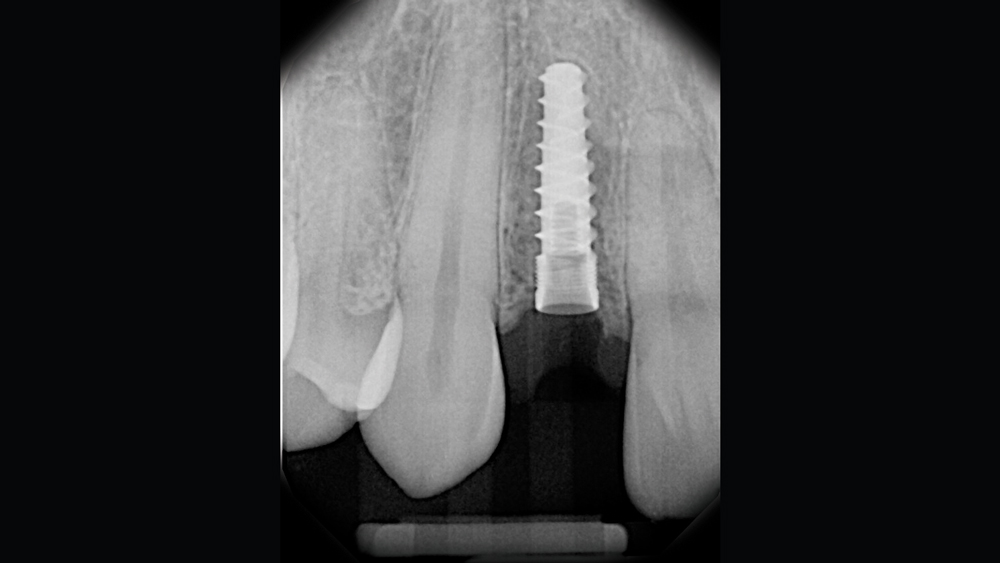

The following case illustrates the efficient, straightforward clinical workflow for placing Hahn Tapered Implants via guided surgery. A digital treatment plan is developed in which a 3.5 mm implant is positioned to support the ideal prosthetic outcome. An immediate provisional crown is designed in concert with the surgical guide and delivered at the time of surgery, helping to produce a predictable, highly esthetic restoration for a demanding case in the smile zone.